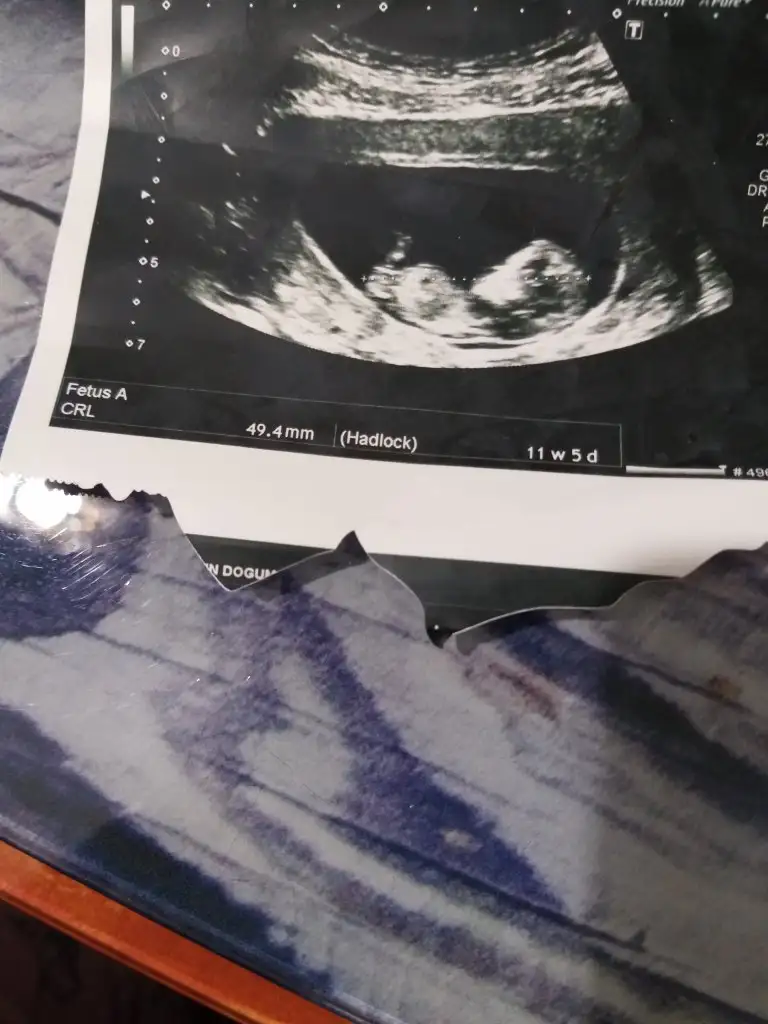

Banada erkek demiştiniz hatta baya net erkek demiştiniz kız diyince doktor şaşırmıştınız bnde çok şaşırmıştım tabi çünkü baya umutlanmıştım 2 kızım var doğal olarak değişik olsun istemiştim tabiki Rabbim in dediği olur ama hala erkek hissediyorum ayrıntılıda pozisyonu tersti cinsiyeti gözükmüyor demişti perinatolog ama 2 doktor kız gibi biride düşük kalitede bir cihazda kız demişti sonra rüyamda bebeğimin isminin koyulduğunu gördüm mavi nüfus kağıdında Ali arif yazıyordu bilemiyorum hala erkek hissediyorum pembe kıyafetleri almama rağmen

az kaldı sonucu görmeye herşey den önce Rabbim sağlıklı ve hayırlı evlatlar nasip etsin bizlere